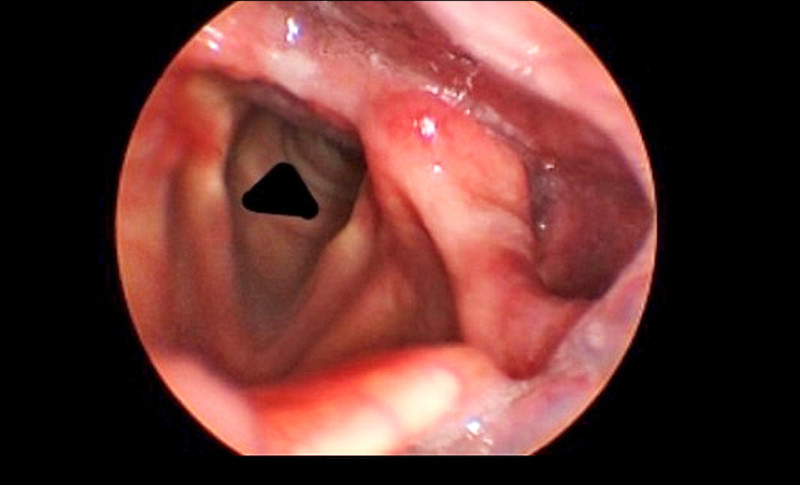

彰基總院長陳穆寬說,患者曾接受甲狀腺手術,術後出現聲音無力、呼吸困難,並伴隨喘鳴聲,內視鏡喉部攝影檢查確定是雙側聲帶麻痺,因患者呼吸道阻塞,伴隨缺氧,院方施予聲帶雷射顯微整形手術,患者術後甦醒時,宛如鬼壓喉嚨的症狀立即消失,呼吸恢復順暢。

陳穆寬指出,正常情況下,雙側聲帶在發聲時閉合,呼吸時張開,讓空氣進入氣管;但患者雙側聲帶麻痺,聲帶無法正常運動,導致氣道狹窄,吸不到足夠空氣,才會出現嚴重喘鳴與呼吸困難症狀。

曾信嘉指出,甲狀腺良性腫瘤手術造成雙側聲帶麻痺,屬於極罕見的嚴重併發症,發生機率低於1%;相較之下,單側喉返神經麻痺導致聲音沙啞的發生率約5%。一旦出現雙側聲帶麻痺,治療時不僅要兼顧發音功能,也必須維持呼吸道通暢與吞嚥功能,手術難度相當高,所幸這名患者經手術後恢復順利,生活也恢復正常。